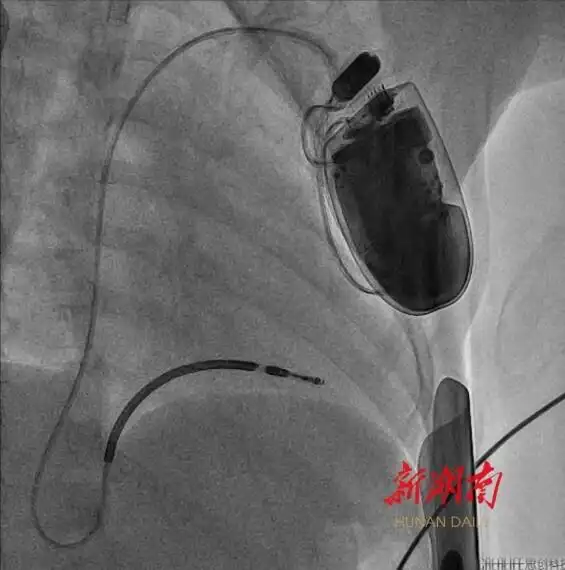

湖南日報4月22日訊(文字/視頻 全媒體記者 周陽樂 通訊員 黃娟 宋青青)今天,記者從湖南省兒童醫(yī)院獲悉,該院血管內(nèi)科陳智主任團(tuán)隊近期成功為一名年僅4歲半、體重16公斤的短QT間期綜合征患兒植入心臟轉(zhuǎn)復(fù)律自動除顫器(ICD)。此為中南地區(qū)年齡最小、體重最低的兒童心臟轉(zhuǎn)復(fù)律自動除顫器手術(shù)案例。

體重輕、血管細(xì)小、皮下脂肪薄……術(shù)前,團(tuán)隊對手術(shù)路徑設(shè)計、導(dǎo)管操作方式、麻醉方案及術(shù)中突發(fā)狀況處理等細(xì)節(jié)進(jìn)行了嚴(yán)密論證。4月16日上午,在麻醉師全程監(jiān)護(hù)下,團(tuán)隊結(jié)合血管超聲的特點,成功經(jīng)腋靜脈,將電極導(dǎo)線精準(zhǔn)送達(dá)右心室心尖部,并通過調(diào)整預(yù)留適合孩子生長的長度,經(jīng)程控測試確認(rèn)最佳起搏閾值后,與ICD裝置完成精準(zhǔn)連接。

經(jīng)過2個小時的努力,手術(shù)順利結(jié)束。術(shù)后,護(hù)理團(tuán)隊為悅悅制定了個性化護(hù)理方案,重點防控感染、導(dǎo)線移位等風(fēng)險,通過多學(xué)科協(xié)作保障醫(yī)療安全。目前,悅悅恢復(fù)狀況良好,未再出現(xiàn)室顫發(fā)作。